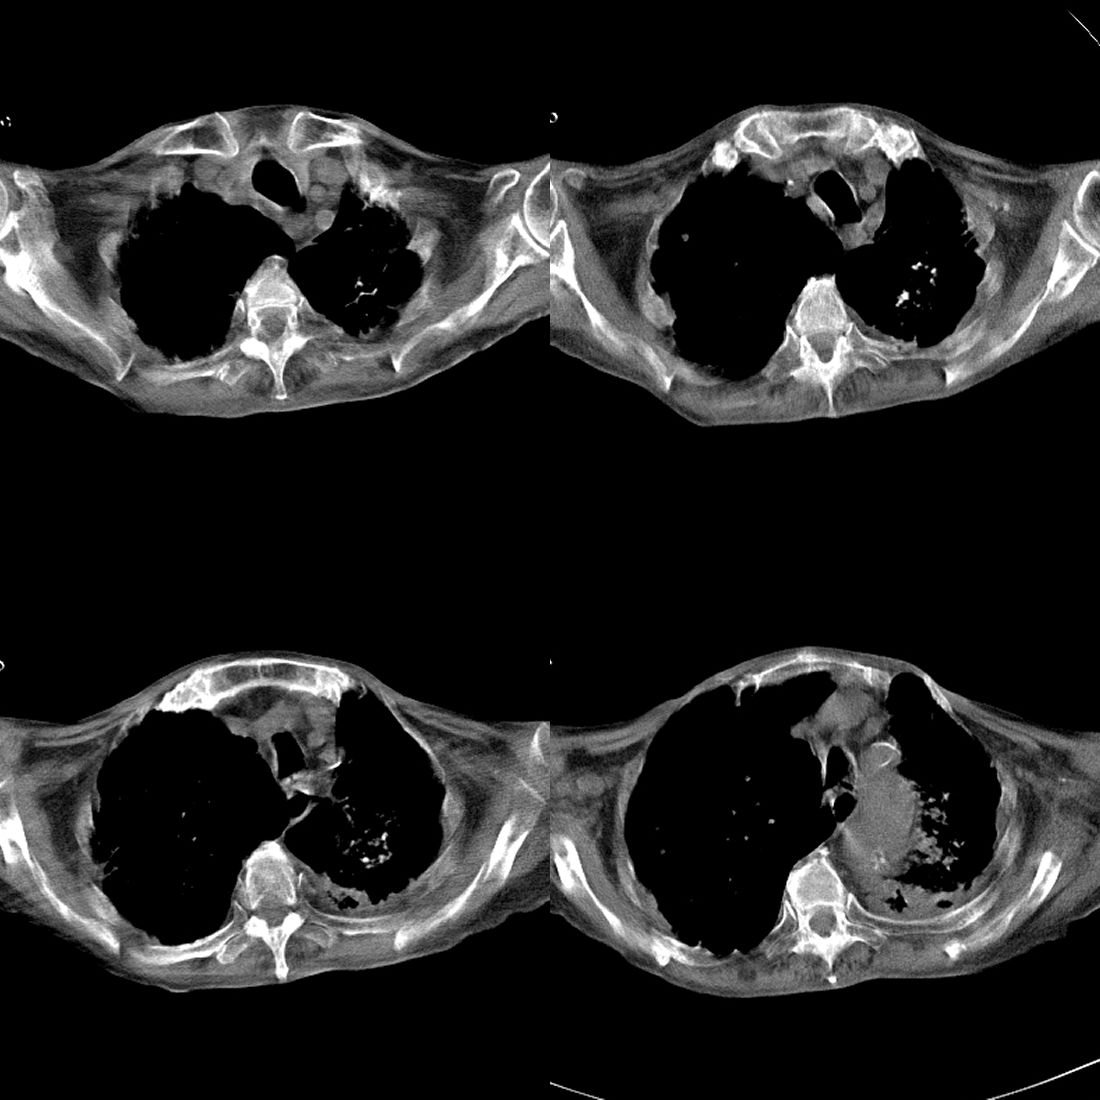

以下是引用zsl6918在2008-11-29 21:51:00的发言:[br]建议追问病史有无粉尘接触史,鉴别是结核还是矽肺。另外,左侧肺门的改变需强化明确,除外占位。

以下是引用liuyue在2008-11-30 6:01:00的发言:[br]双肺继发性肺结核;左侧包裹性积液;建议增强化或支气管镜检查除外左肺占位性病变.

以下是引用吴承学在2008-11-30 8:02:00的发言:[br]双肺继发性肺结核;左侧包裹性积液;建议增强化或支气管镜检查除外左肺占位性病变.[br]